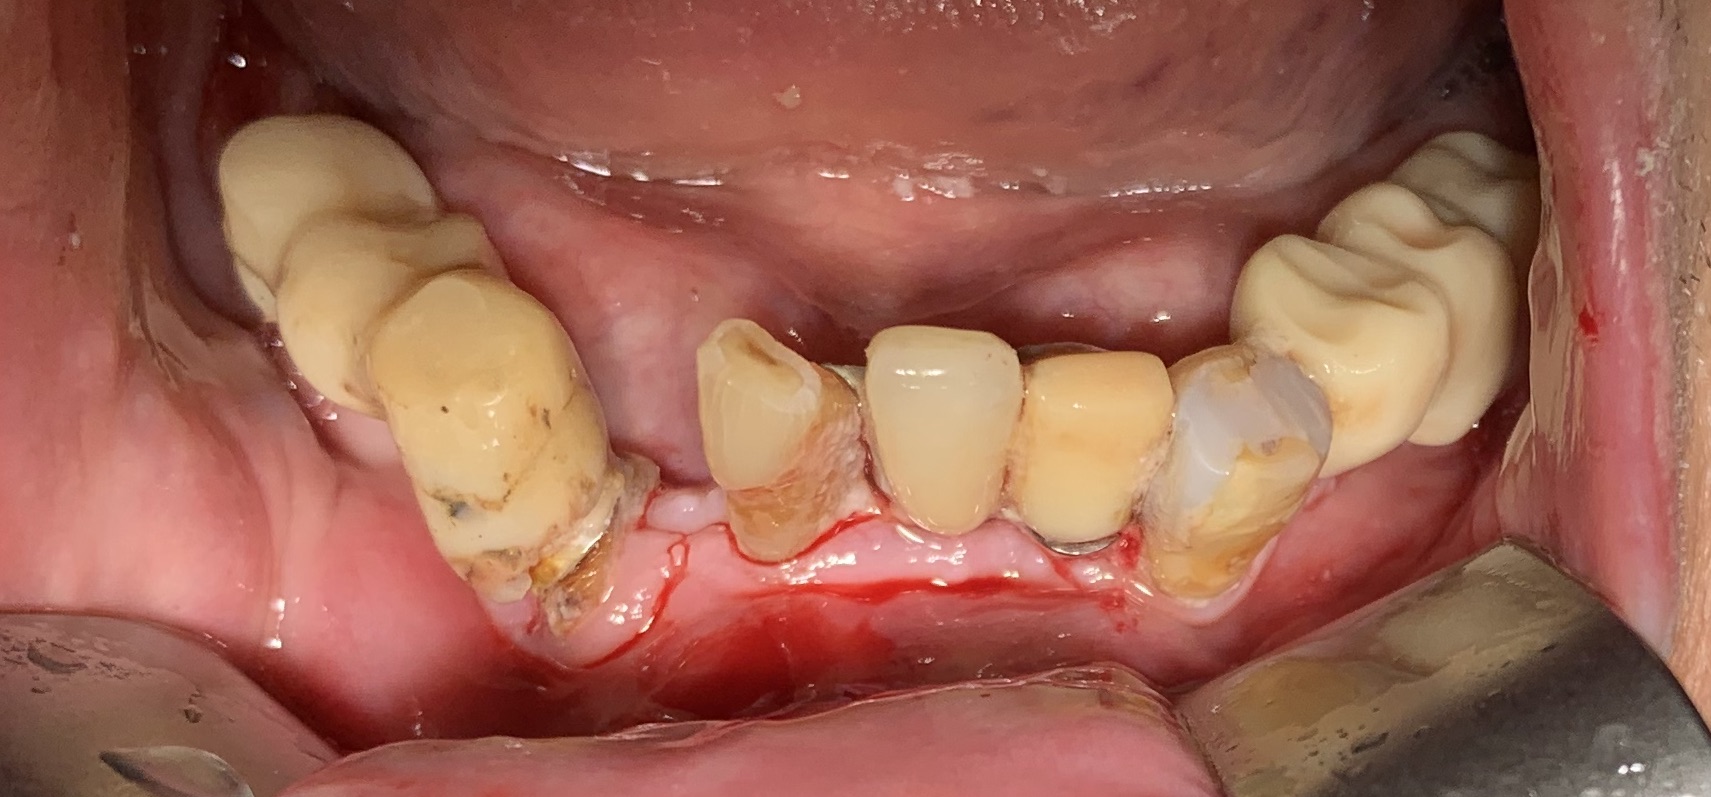

1 - UN CASO INCISIVO

Frattura di elemento incisivo inferiore 31 e riabilitazione implantare